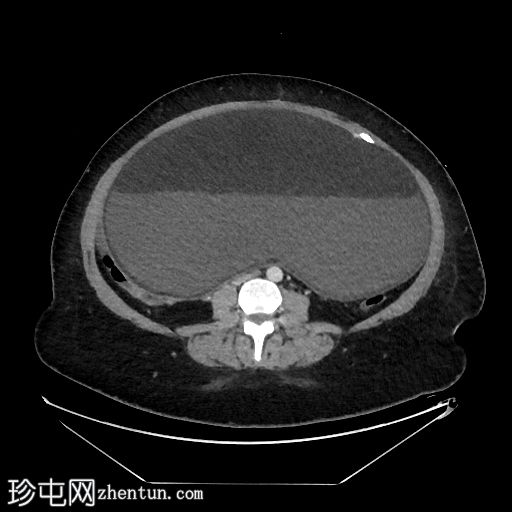

冠状位增强扫描(门静脉期)

盆腹腔巨大囊性病变,可见脂肪液平面及漂浮球征(脂肪/软组织团块漂浮)

病变周边可见钙化灶

左侧附件呈旋涡状外观,提示附件扭转

以上影像学表现提示左侧卵巢成熟囊性畸胎瘤伴附件扭转

右侧附件病变主要由脂肪组成,伴钙化及软组织成分